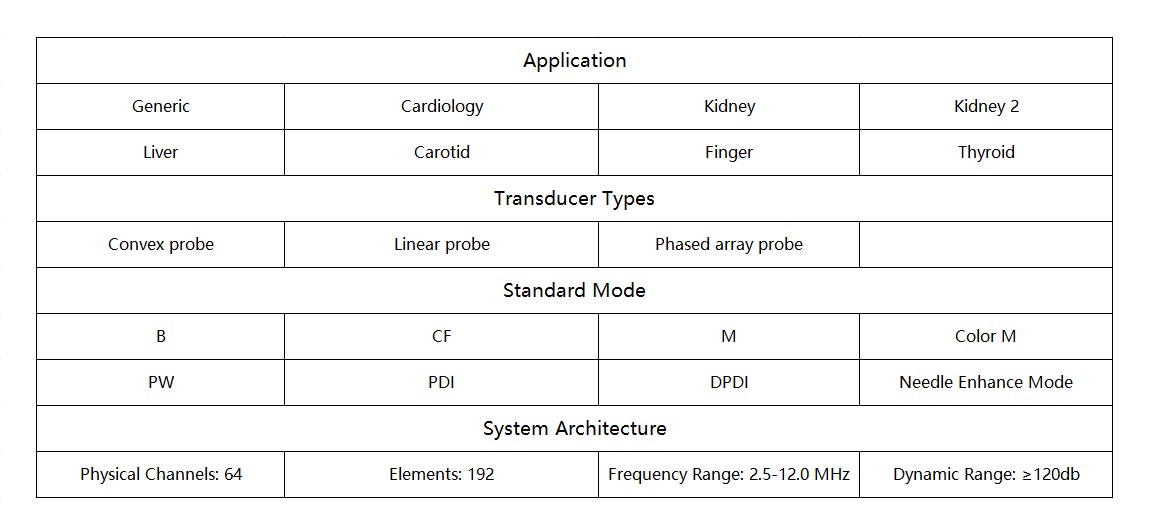

Can be connected with every terminal of iOS Android and Windows system

Battery:Removable big capacity lithium battery

Display Mode:B, M, CF, PW, PDI, DPDI, Needle Enhancement

Measure Function:OB,distance,area of a circle,Velocity,blood flow measure,fetal heart,heart rate